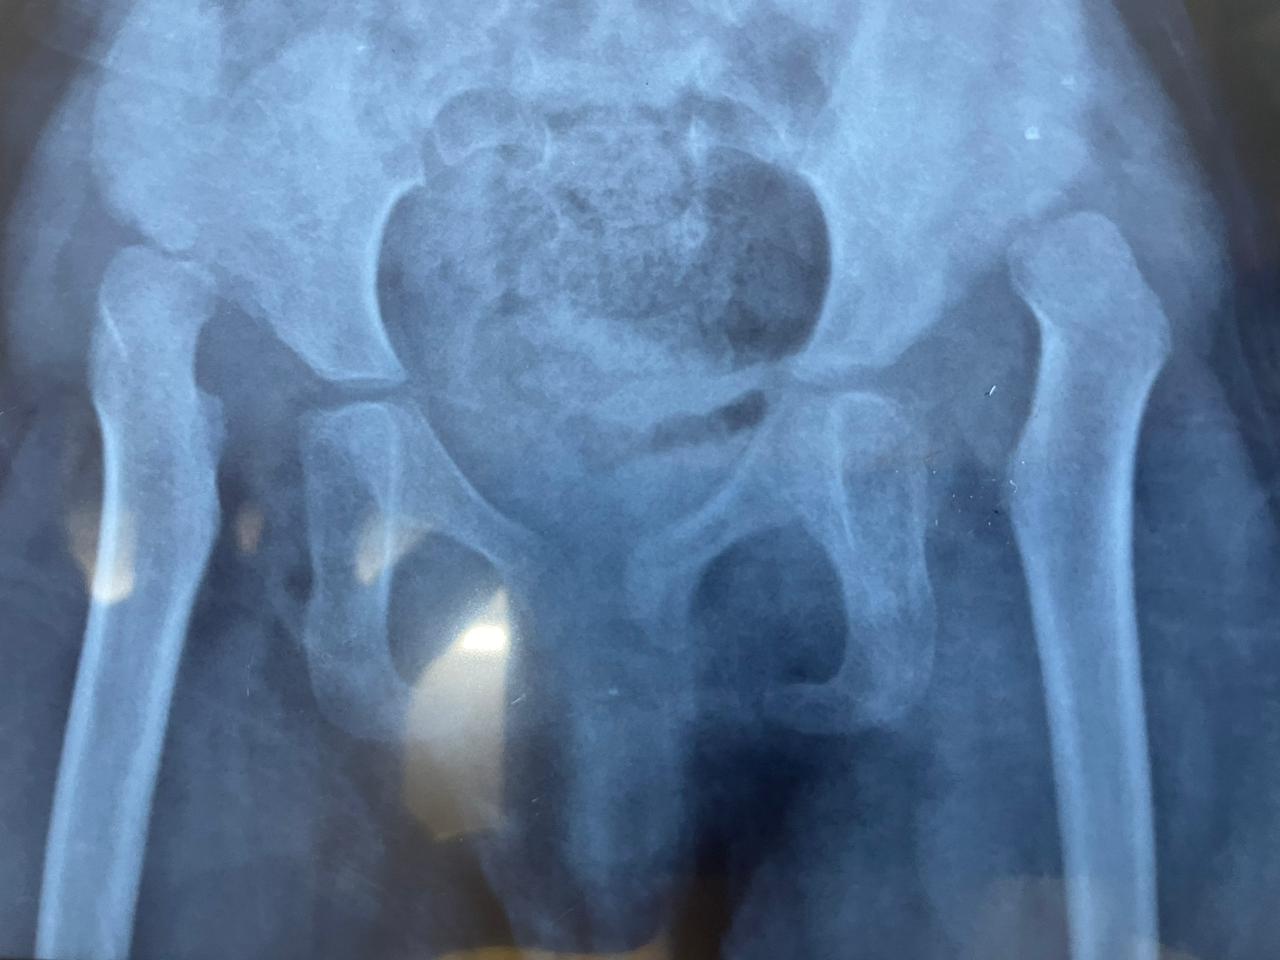

Developmental Dysplasia of the Hip (DDH)

DDH is characterized by abnormal acetabular morphology, often leading to pain and instability in the hip. Timely diagnosis and management are essential, especially since untreated DDH can lead to further complications like hip osteoarthritis.

Developmental Dysplasia of the Hip